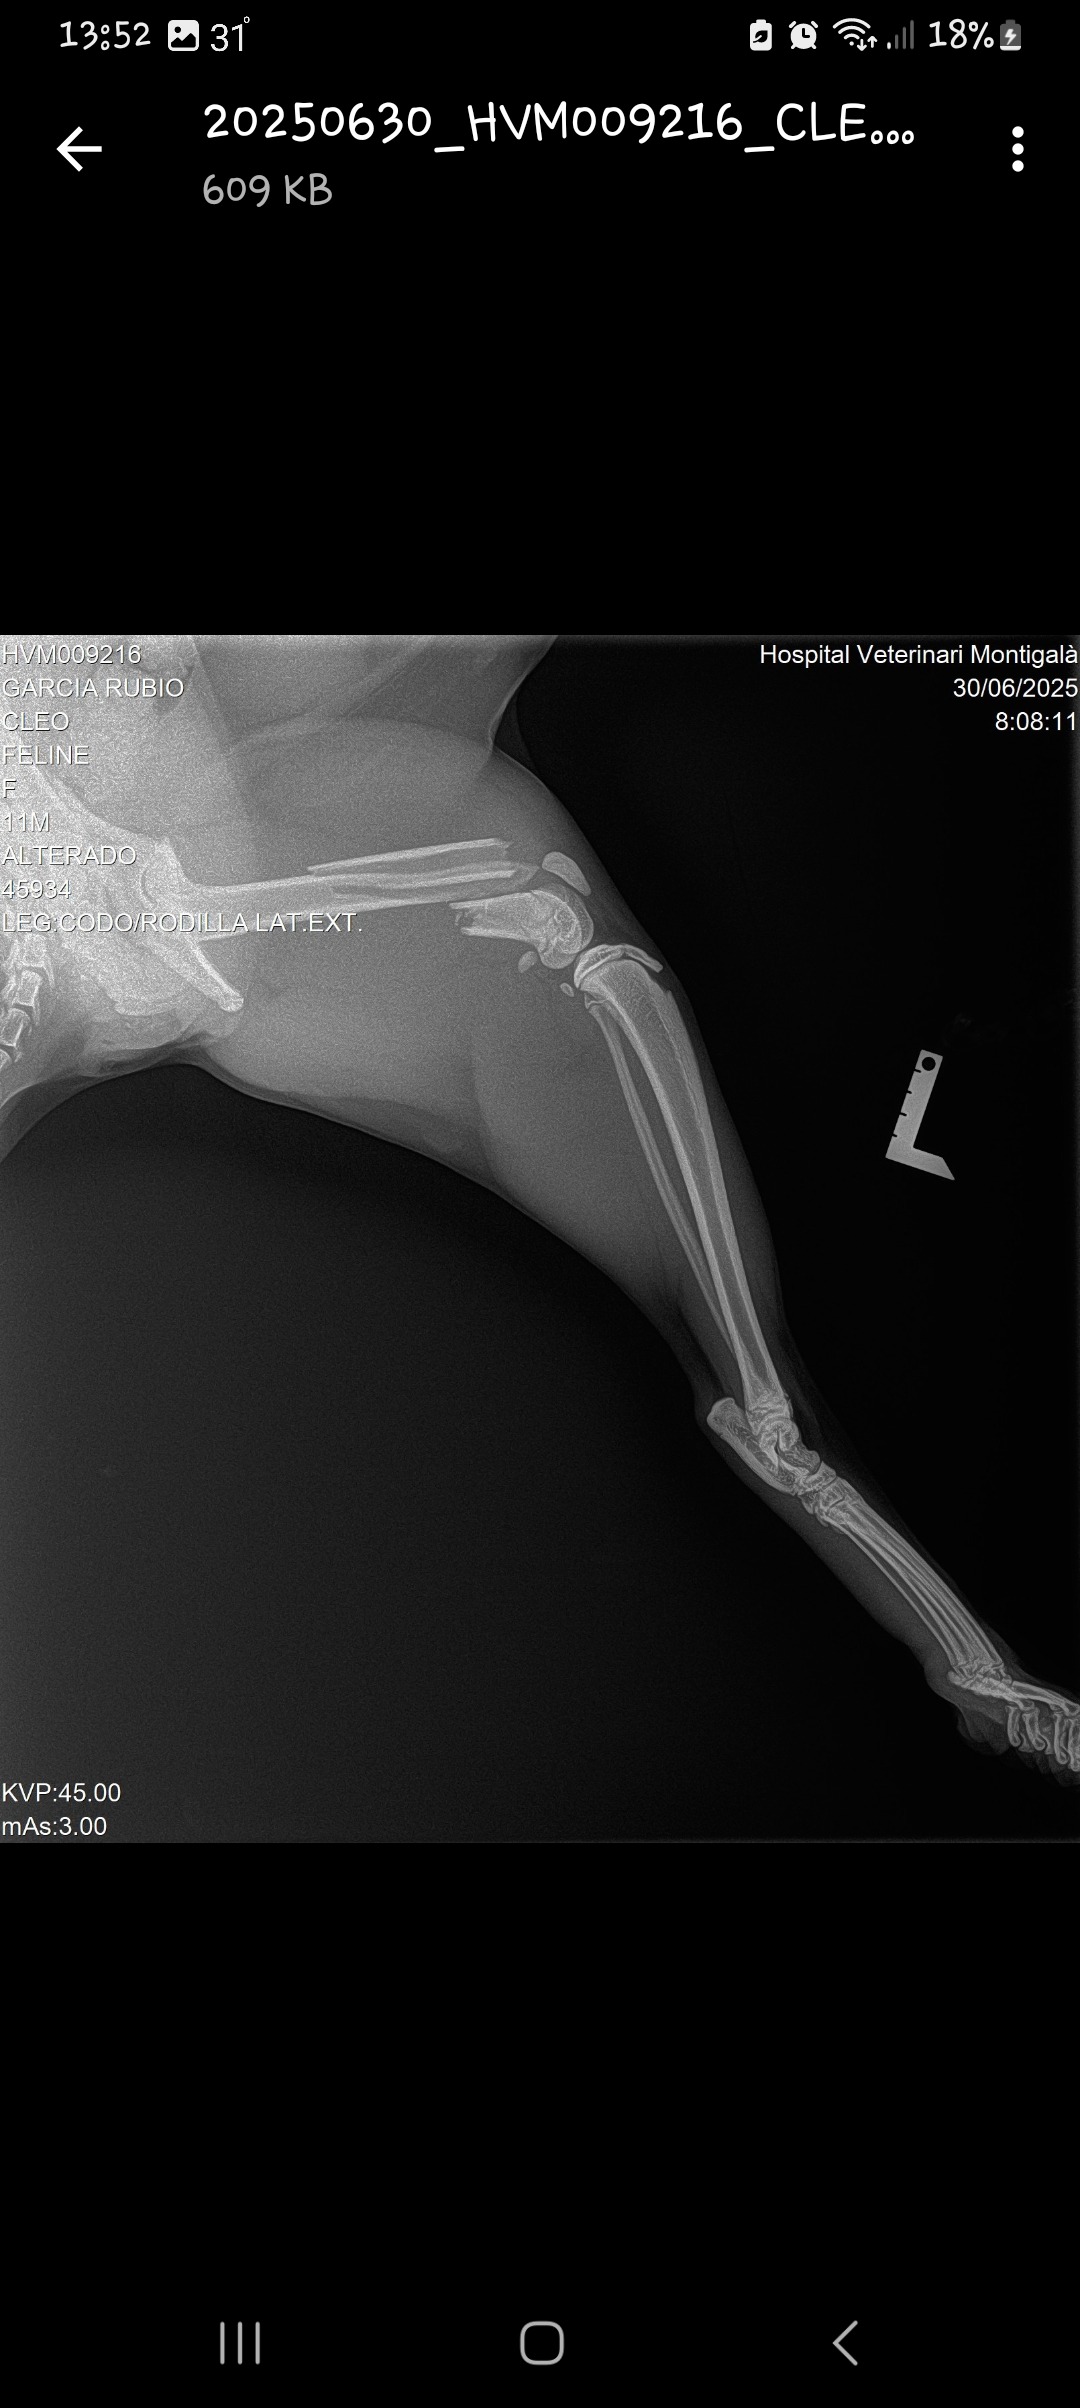

Hola me llamo Laura y estoy rescatando dinero para Cleo mi gata de 9 meses..se cayó de un 2 piso y la tienen que operar con carácter de urgencia de una patita sino la perderá...es muy urgente sino se opera rápido puede engangrenarse y perder la pata....porfavor SOS